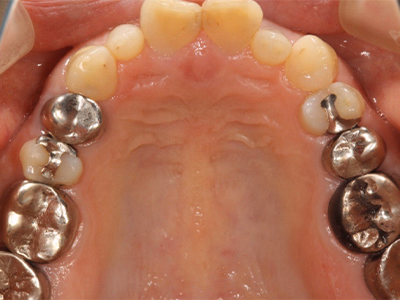

全顎修復

治療前後写真

治療前

治療後

年齢・性別

43歳・女性

来院理由

銀歯を白い歯に治したい

治療内容

マイクロスコープ下でカリエス除去後、セラミック(インレー・クラウン・ラミネートべニア)で全顎的に修復しメンテ移行

治療期間

約2ヶ月

費用

- ラミネートべニア(2本)297,000円

- セラミックインレー(2歯)143,000円

- セラミッククラウン(6歯)1,023,000円

リスク・副作用

再補綴時の歯髄損傷リスク

残存歯質が少ない場合の破折リスク

医院コメント

色・形態・咬合を総合的に整え、審美性と機能性のバランスを長期目線で最適化。